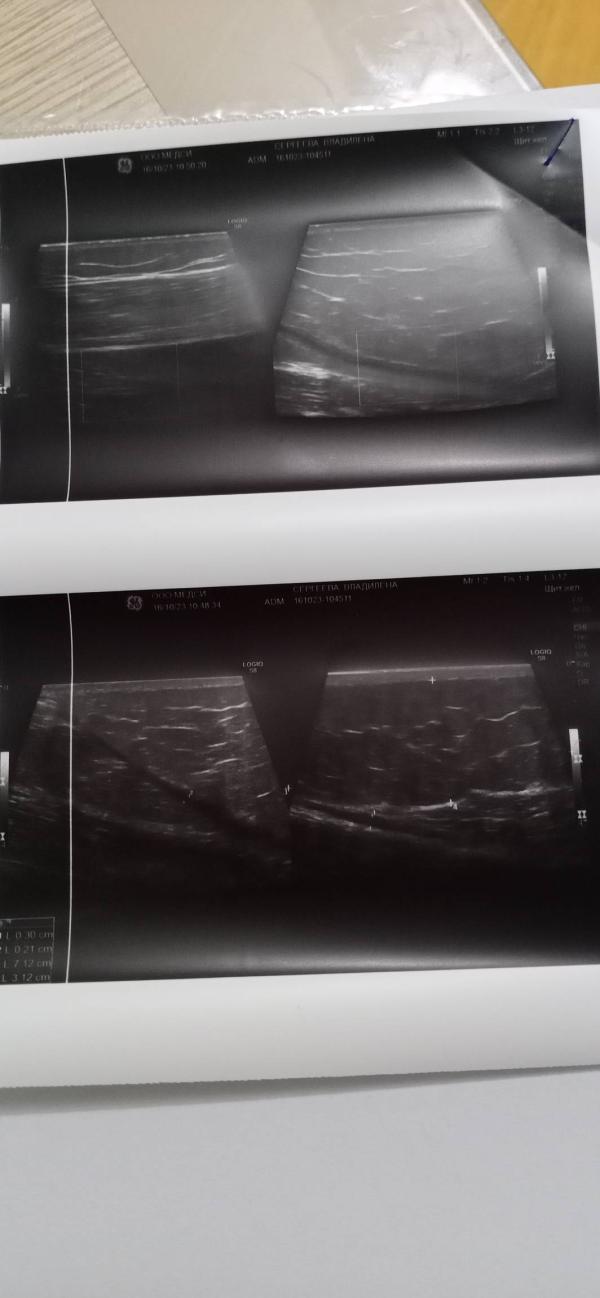

Сходили мы на УЗИ и даже два, на ренген.

И честно сказать были удивлены, а даже шокированы. У Влады оказывается был перелом, а что это за образование в виде шишки ни кто незнает.

Послал нас дообследоваться и возвращаться. Назначил нам новое УЗИ и рекомендовал Бурдину Е. Б. в "Медси" и конечно же МРТ.

Голопом я полетела в больницу по прописке, чтоб нам дали направление на МРТ. К сожаление сразу нас не записали, только поставили в очередь. А вот УЗИ сходили сделали. Диагноз доброкачественная опухоть.